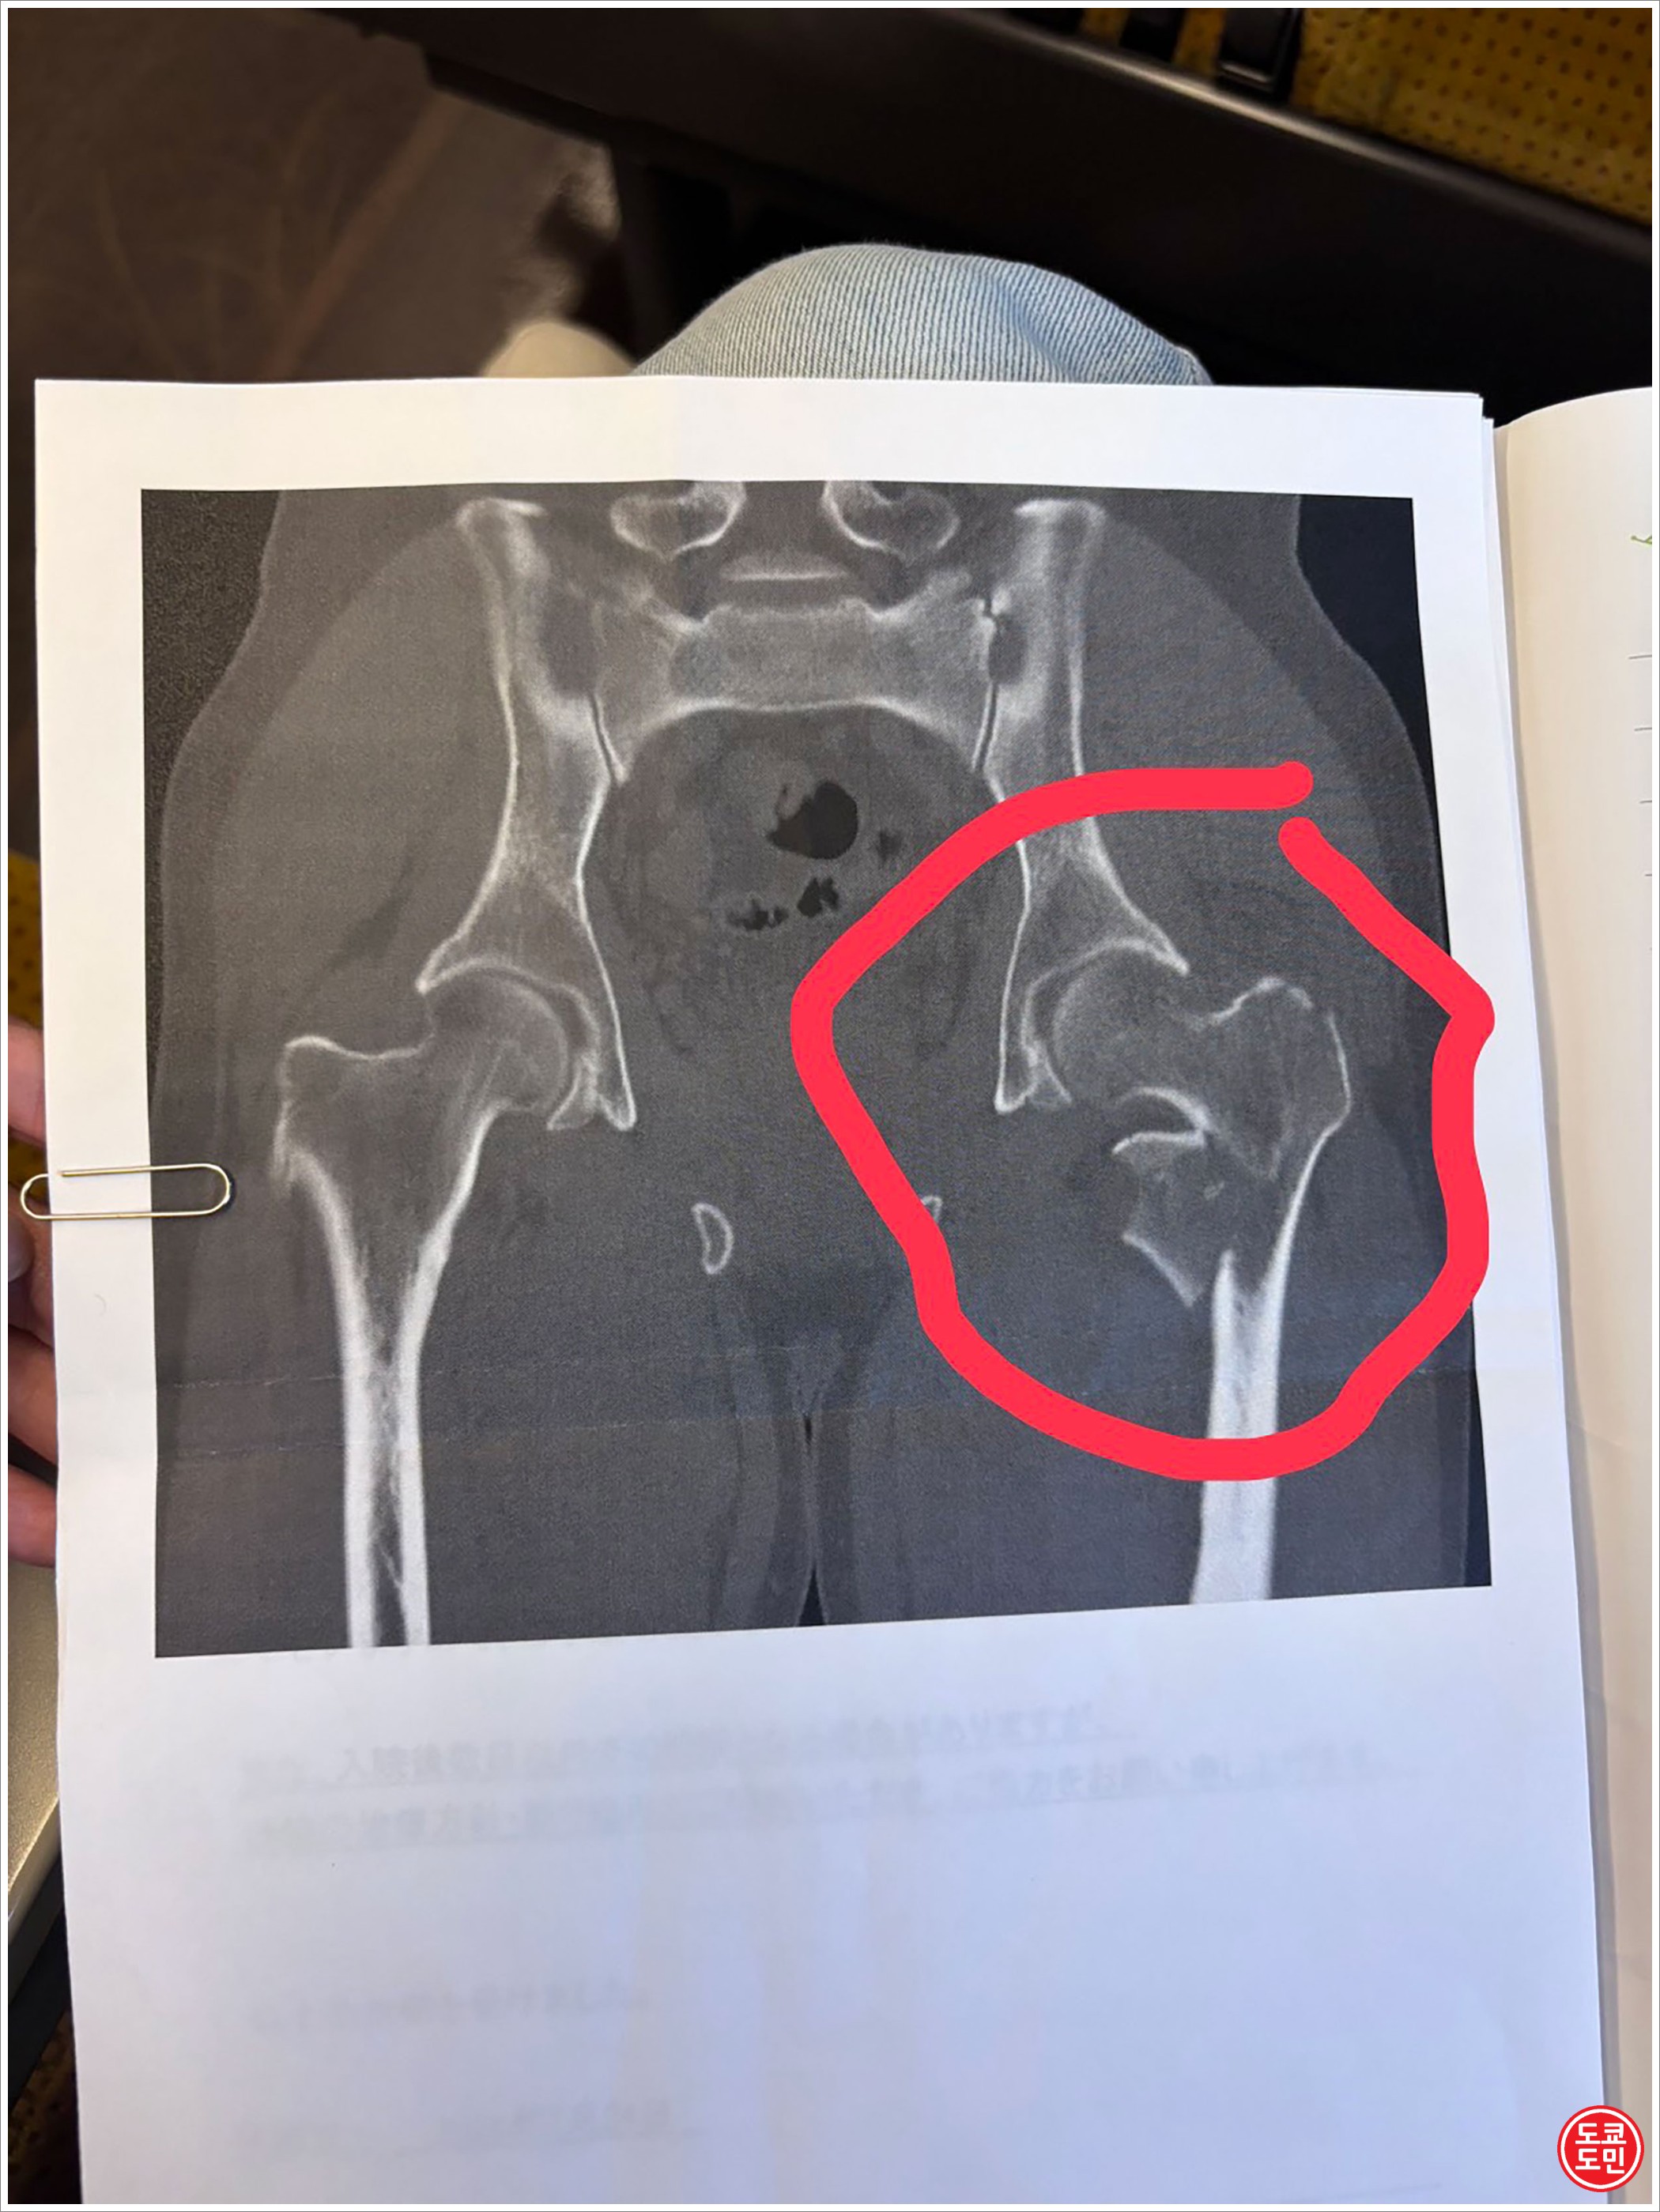

아무튼 왼쪽 다리의 X레이 사진을 보니 금도 가고 뼈도 좀 부서졌다고 한다.

왼쪽 다리의 대퇴골 골절로 인한 수술은 2026년 1월 27일에 이뤄졌다.

결과적으로는 뼈에 철심을 박고 나사를 조아서 고정을 시켰고, 뼈가 완전히 붙기까지는 3~6개월정도 걸린다고 당분간 조심하라고 하셨다.